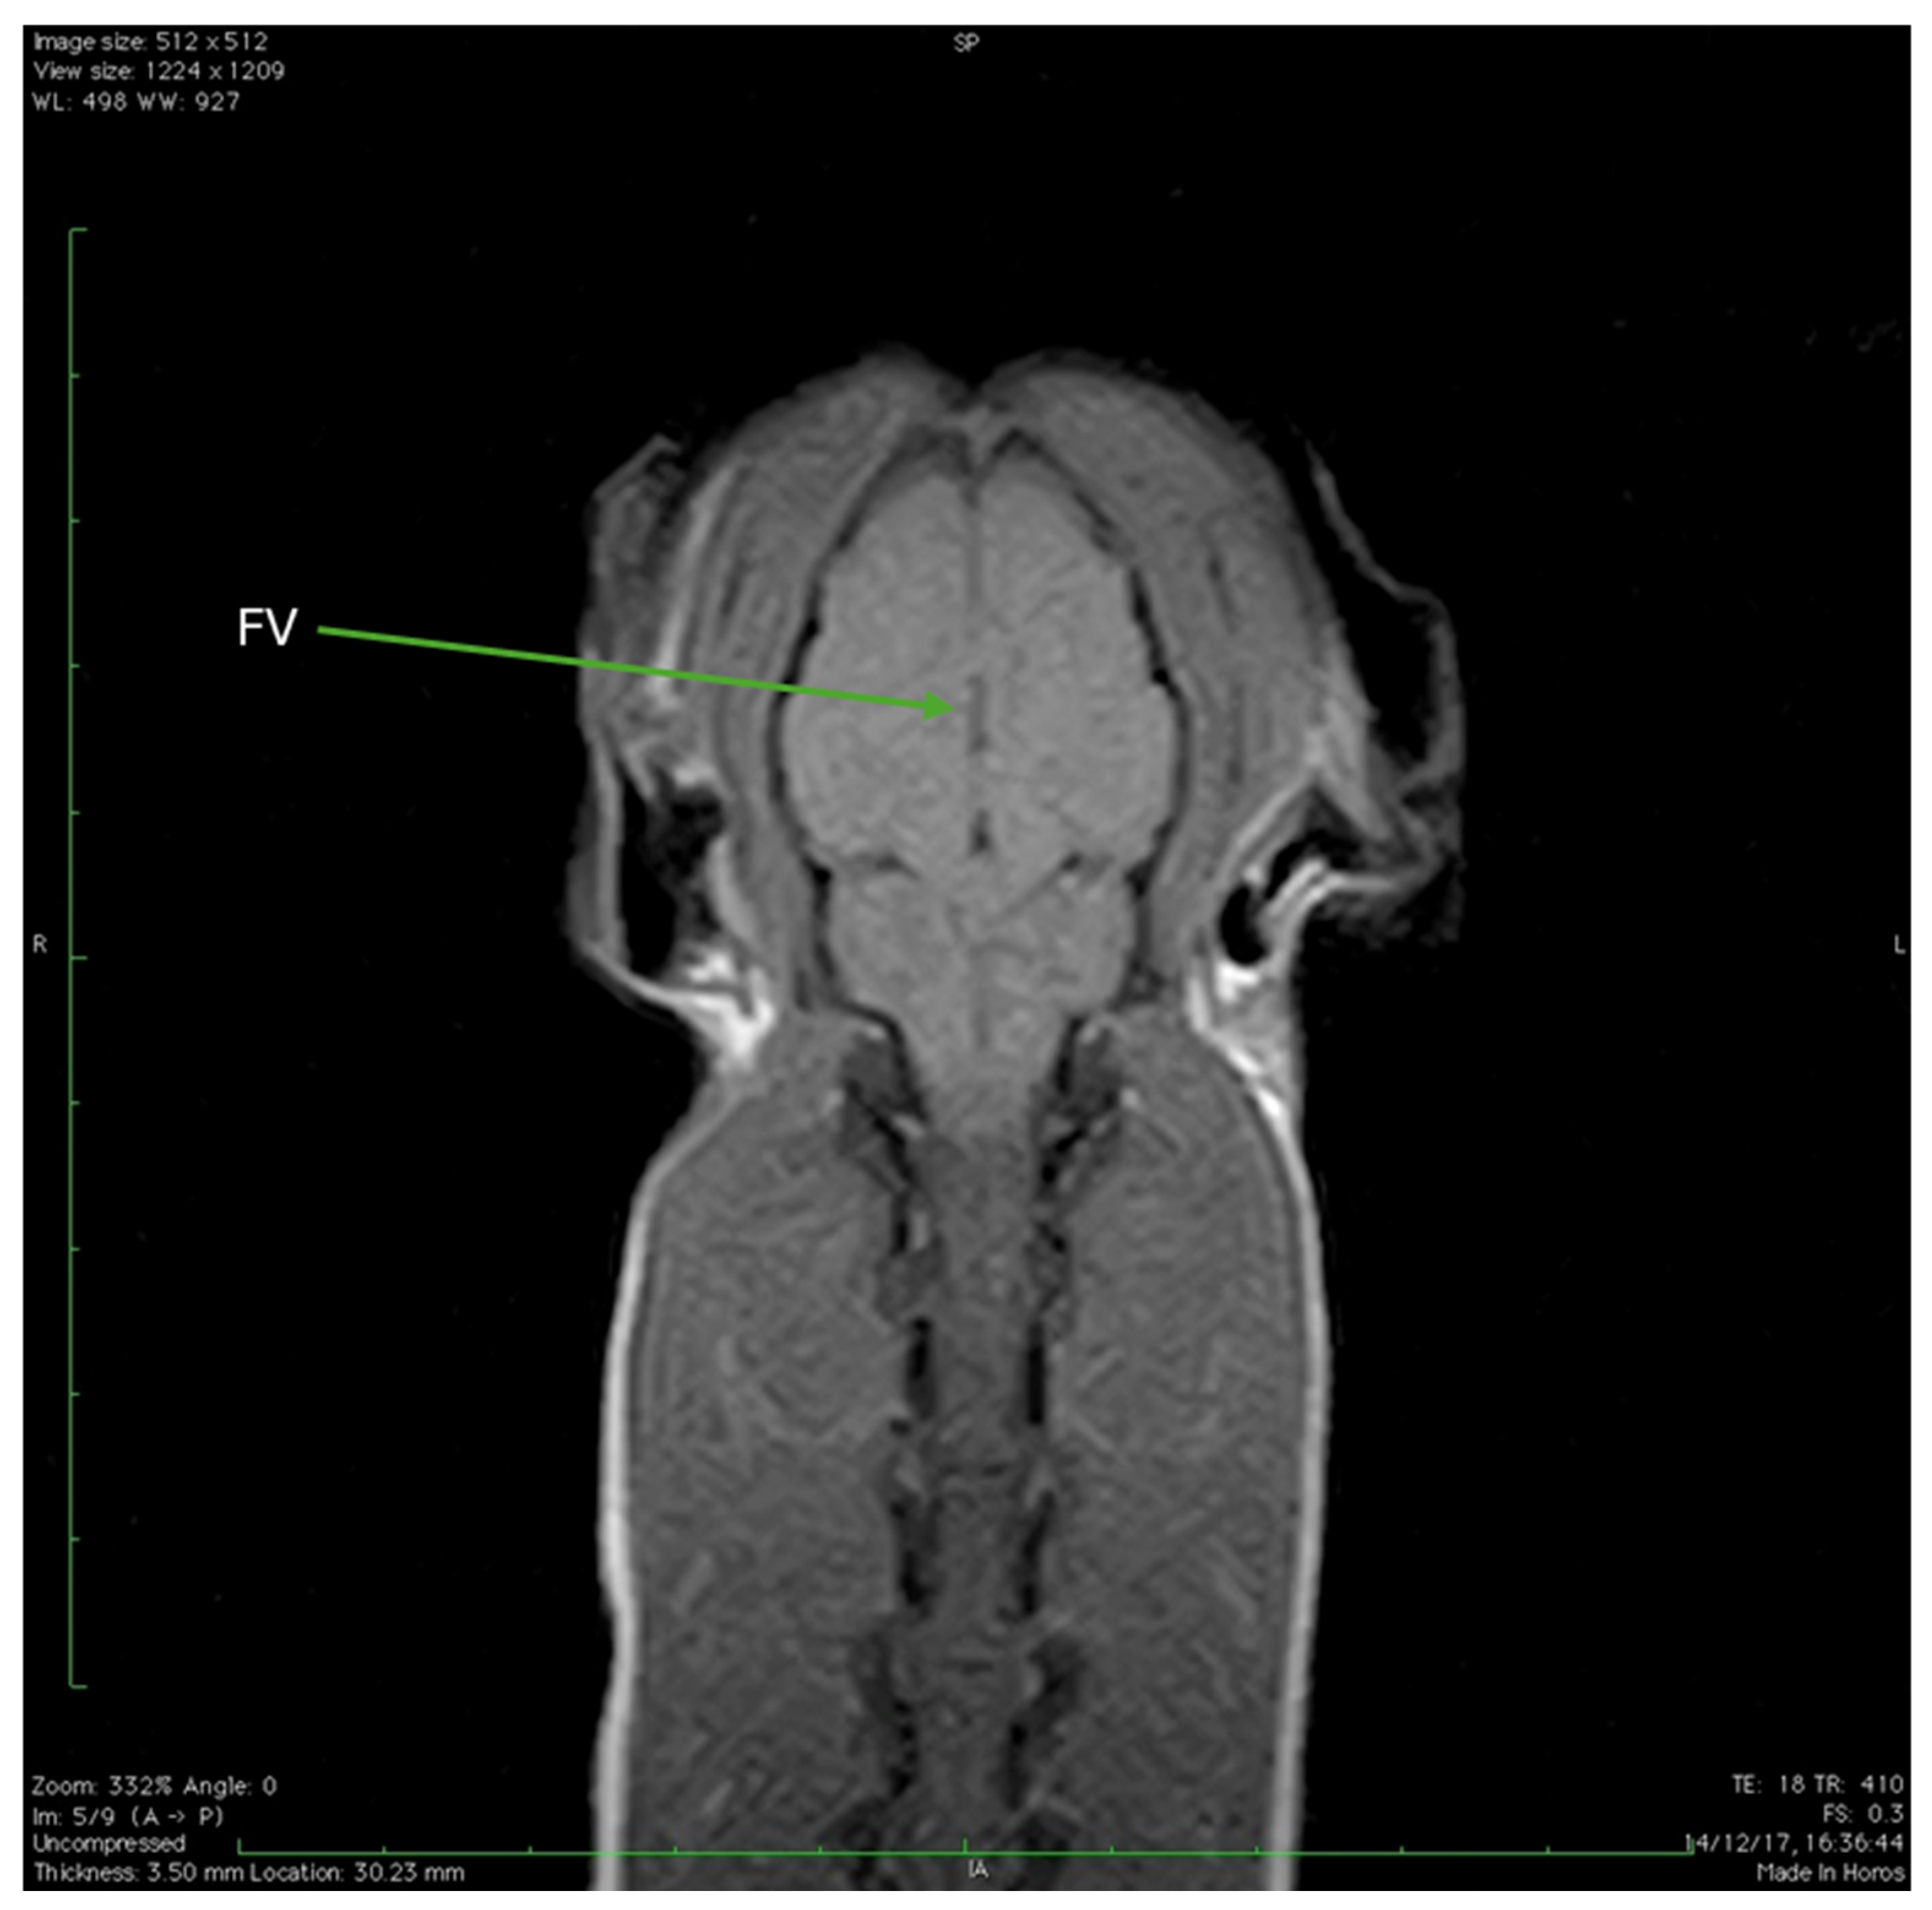

| FV | Fourth ventricle |